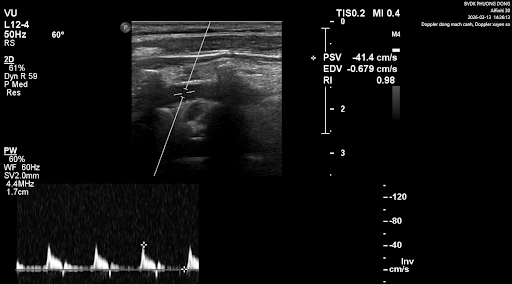

Bệnh nhân nữ có triệu chứng yếu nửa người trái, các bác sỹ siêu âm thấy động mạch cảnh và động mạch đốt sống đoạn bên ngoài sọ không có xơ vữa trên siêu âm 2D nhưng trên siêu âm doppler xung, phổ doppler lại tăng trở kháng, rất gợi ý có hẹp ở đoạn trong sọ.